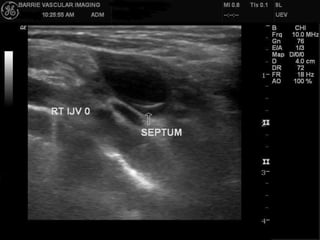

CRITERION 3 :IJV STENOSIS

a) Severe reduction of the CSA of IJV

in th e supine position <0,3 cm2

which does not increase with

Valsalva manoeuvre (performed at

the end of the examination).

b) Intraluminal defects such as webs,

septa or malformed valves

combined with hemodynamic

changes (increased velocity,

absence of flow, reflux/bidirectional

flow etc).

M-mode investigation of leaflets

may clarify if they are mobile or not.

a) Severa riduzione dell’area della VGI

in posizione supina (inferiore a 0,3

cm2) non influenzata dalla manovra

di Valsalva (manovra da effettuarsi

al termine dell’esame).

b) Anomalie endoluminali come

membrane, setti o valvole

malformate in combinazione con

turbe emodinamiche (incremento

della velocità di flusso, assenza di

flusso, reflusso/flusso bidirezionale

ecc.). Studio con M-mode sulla

mobilità o meno dei lembi valvolari.

Stenosi delle Vene Giugulari interne:

A: setto- B: membrana ostruente il vaso

C: annulus- D: lembi valvolari

malformati